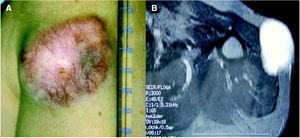

A la exploración física se apreciaba una tumoración sobreelevada, intradérmica de 8 × 4 cm de tamaño, muy indurada e infiltrada a la palpación (fig. 1A). La zona superficial presentaba capilares ramificados y dilatados con zonas blanquecinas, nacaradas y brillantes de aspecto cicatrizal. La resonancia magnética de la zona afectada efectuada para valorar la extensión del tumor, reveló un desplazamiento del músculo deltoides y la existencia de infiltración muscular por la lesión en dicho músculo (fig. 1B). La biopsia cutánea mostró la presencia de una tumoración en la dermis con infiltración del tejido celular subcutáneo, constituida por células fusiformes de núcleo elongado con un patrón estoriforme y otras células más pleomórficas con un mayor índice mitótico, con una disposición en largos fascículos, adoptando un patrón en espina de pescado (fig. 2A). El estudio inmunohistoquímico mostró una tinción intensa citoplasmática con CD34 en más del 90 % de las células fusiformes con patrón estoriforme, con mínima inmunotinción en las células pleomórficas de la zona de patrón en espina de pescado (fig. 2B). El factor XIIIa fue negativo en la población tumoral.

Fig. 1.--A) Tumoración localizada en la parte proximal del brazo de 8 × 4 cm. B) Resonancia magnética nuclear: infiltración por la tumoración del músculo deltoides.